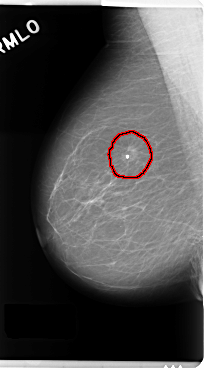

FILE: C_0190_1.RIGHT_MLO.OVERLAY

TOTAL_ABNORMALITIES 1

ABNORMALITY 1

LESION_TYPE CALCIFICATION TYPE ROUND_AND_REGULAR DISTRIBUTION CLUSTERED

LESION_TYPE MASS SHAPE OVAL MARGINS SPICULATED

ASSESSMENT 5

SUBTLETY 5

PATHOLOGY MALIGNANT

TOTAL_OUTLINES 1

BOUNDARY